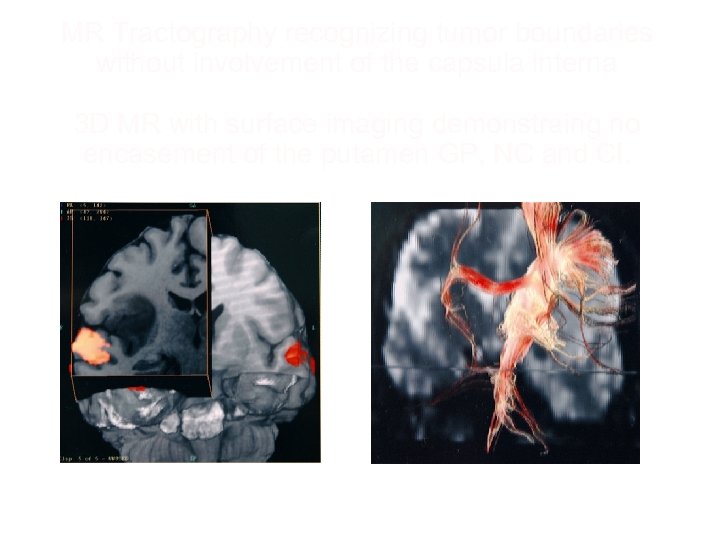

Tractography of capsula interna axial view and temporal opercular uditive area in right hemisphere

MR Tractography recognizing tumor boundaries without involvement of the capsula interna 3 D MR with surface imaging demonstraing no encasement of the putamen GP, NC and CI.